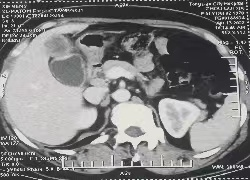

患者女性,51岁,因间断右上腹疼痛1年余入院,既往无特殊疾病史。入院后经完善相关检查提示:胆囊底占位性病变,并已侵透胆囊全层。通过术前充分评估和讨论,在与患者及家属充分沟通后,祁向军主任医师结合患者自身情况决定行腹腔镜下胆囊癌根治术,手术包括胆囊床区肝组织楔形切除和腹腔淋巴结的清扫。

胆囊癌是胆道系统较常见的恶性肿瘤,具有发病隐匿、侵袭性强、容易发生淋巴结转移等特点,多数患者发现时已属于晚期。目前治愈胆囊癌的唯一机会仍是手术切除。相较于传统开腹手术,腹腔镜下胆囊癌根治性切除术具有创伤小、恢复快的优势,患者术后可早期下床活动,正常进食,减少疼痛、粘连性肠梗阻等并发症,提高术后生活质量。